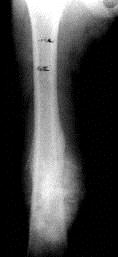

问题 病历摘要: 患者 ×××,男性,9岁,右大腿下段肿痛3个月。查体:T 36.7℃, P 80次/分,右大腿下段皮肤肿胀,血管恕张,触痛(+),质硬,叩击痛(+),其余(-)。实验室检查:ESR 20mm/L。 关于成骨肉瘤以下叙述哪些是正确的?

选项 A、骨肉瘤的病理诊断主要依据是要有肉瘤性的基质组织,以及由它直接转变而成的骨样组织及骨小梁 B、骨肉瘤常发生肺转移 C、骨肉瘤好发于干骺端 D、骨肉瘤好发的部位是:股骨远端及胫骨、肱骨的近端 E、大多数发生在10~20岁,女性多于男性,为2:1

答案 ABCD